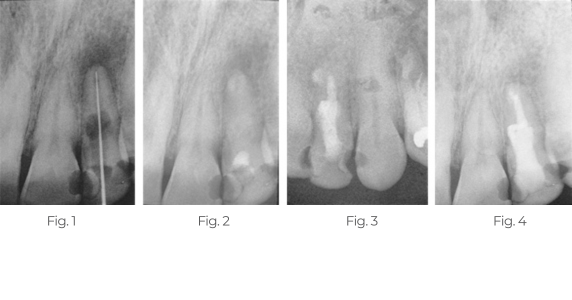

Behandlung von periapikalen Läsionen und interner Resorption

Der Patient stellte sich mit erheblichen Beschwerden und extremer Empfindlichkeit gegenüber Hitze, Kälte und Perkussion vor.

Abb. 1: Das diagnostische Röntgenbild zeigt eine interne Resorption und eine periapikale Läsion im linken Seitenzahnbereich des Oberkiefers. TempCanal wurde bei diesem Besuch eingesetzt (nicht gezeigt).

Abb. 2: Die 3 Monate später aufgenommene Röntgenaufnahme zeigt, dass TempCanal an Ort und Stelle ist und eine periapikale Heilung stattfindet.

Abb. 3: Die nach 13 Monaten aufgenommene Röntgenaufnahme zeigt den mit Pulpdent Root Canal Sealer unter Verwendung der Pulpdent Pressure Syringe obturierten Wurzelkanal. Beachten Sie die leichte Extrusion des Sealers über den Apex hinaus und den mit Sealer obturierten internen Resorptionsraum.

Abb. 4: Die nach 19 Monaten aufgenommene Röntgenaufnahme zeigt eine kontrollierte interne Resorption und eine abgeheilte periapikale Läsion. Beachten Sie die Lamina dura. Außerdem wurde ein Teil des Root Canal Sealers entfernt und der gesamte Zahn mit Pulpdent® HardCord Dual Cure Composite-Restaurationsmaterial unter Verwendung von DenTASTIC® als Haftvermittler verstärkt.